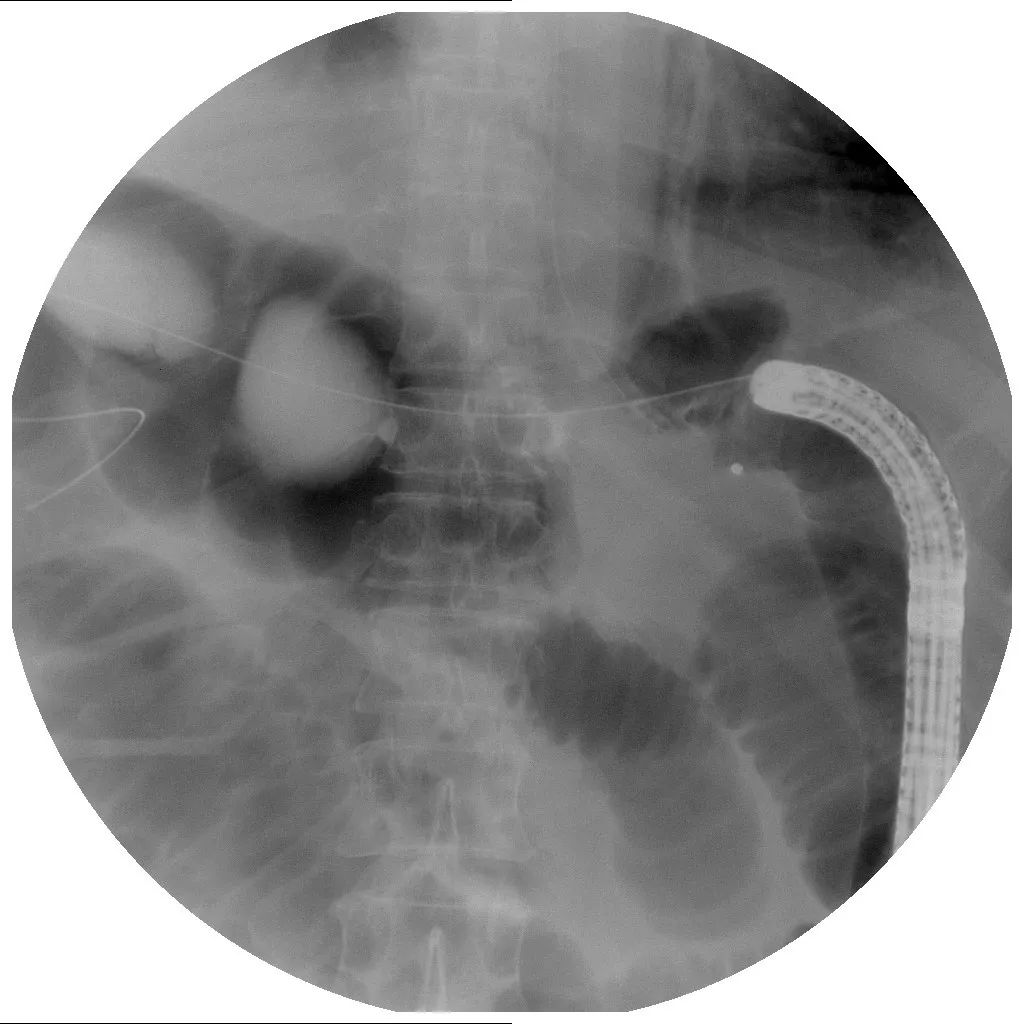

2018年7月初行结肠支架置入术(图4、图5、图6)。

图4 结肠支架置入术

图5 结肠支架置入术